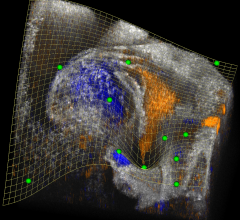

Once considered an adjunct brain cancer therapy and a last-resort treatment, noninvasive radiosurgery has evolved ...

Feb. 26, 2026 — GT Medical Technologies, a company focused on improving the lives of patients with brain tumors, has ...